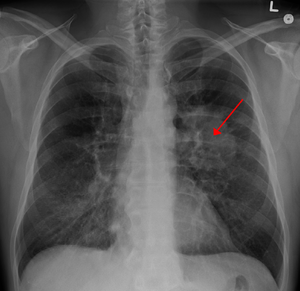

肺癌晚期症状有哪些

患了肺癌,很多的人并不会马上就察觉。而且肺癌的早期症状不是太明显,所以一般患者在发现自己患有肺癌时已经是中晚期了,那么 肺癌晚期症状 有哪些呢?      水肿:面、颈部水肿是 肺癌晚期症状 中比较常见的,若是肿瘤出现侵及纵隔右侧压迫上腔静脉 ...

常见的肺癌早期症状

在肺癌病人中,咳嗽、咯血咳嗽是最常见的 肺癌早期症状 。咯血则最有诊断意义,多为痰中带血丝。凡呼吸道症状超过两周经治不愈,尤其是痰带血、干咳或老年慢性支气管炎病人,近期咳嗽声音或性质改变,要高度警惕肺癌的可能。由于咯血的量少或间歇出现, ...